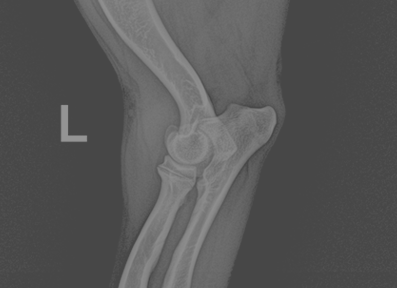

전십자인대 질환 (Cranial Cruciate Ligament Disease)

전십자인대 파열은 반려견에서 가장 흔한 무릎 관절 질환으로, 심할 경우 보행이 어렵고 심한 통증을 유발합니다. 본원은 뼈 구조, 체중, 활동 수준 등을 고려하여 TPLO, CTWO 등 다양한 수술 방법 중 가장 적합한 수술법을 선택해 맞춤 치료를 진행합니다. X-ray와 CT 영상을 통해 인대 손상 정도와 관절 상태를 정밀하게 진단하고, 수술 전 시뮬레이션을 통해 오차를 최소화합니다. 수술 후에는 통증 관리와 재활 운동, 근력 강화 프로그램을 통해 기능 회복을 돕고 재발을 예방합니다.